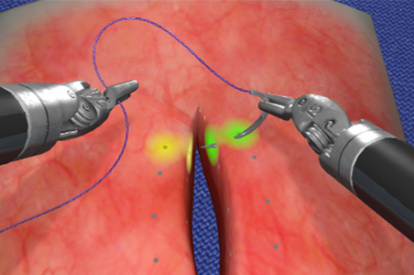

Robotic basic tasks modules allow the user to familiarize with and master the fundamental aspects of robotic skills, while clinical procedure modules let surgeons immerse themselves into partial or entire robotic virtual procedures.

Get a glimpse of the exercises included in the RobotiX Mentor, from the fundamental aspects of instrument manipulation to a variety of full procedures.

- Highly realistic graphics of human anatomy and simulation of tissue response to instruments

- Complication management: simulation of errors and bleedings

Robotic Cholecystectomy Module

Inguinal Hernia Module

Hysterectomy Procedural Tasks Module

Hysterectomy Procedure Module

Vaginal Cuff Closure Module

Robotic Prostatectomy Module

Right Hemicolectomy Module

Lobectomy Module